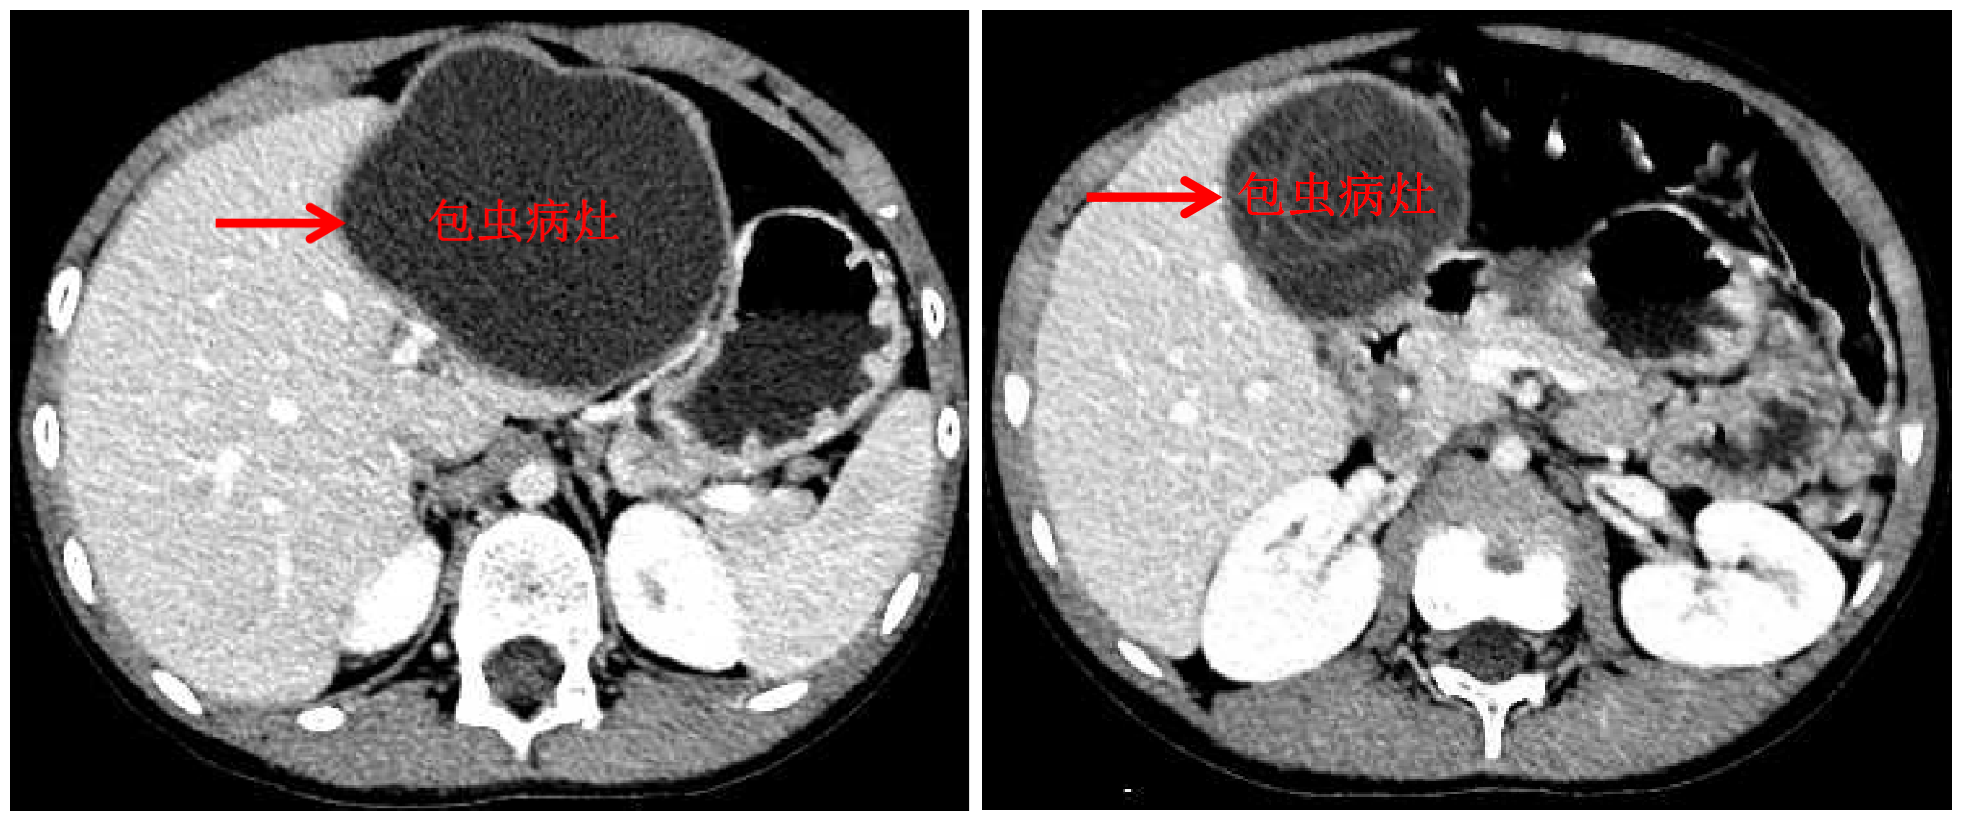

mk(中国)网10月13日电 国庆前,8岁的小扎西被父亲带到了西藏大学附属拉萨市人民医院普外科,此次距离孩子确诊肝包虫病已有一年之久。腹部影像显示,小扎西体内的囊型肝包虫病已经侵袭了左肝大部。

包虫病灶